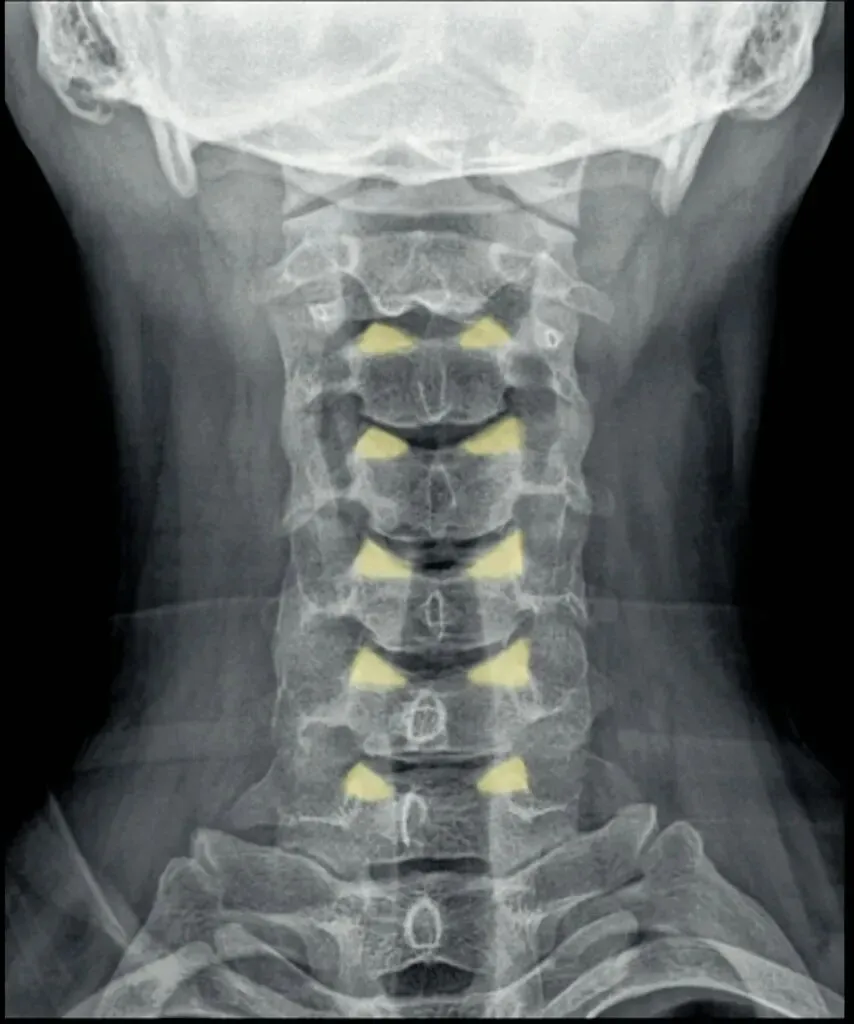

五间是指颈椎椎间隙的变化,主要在颈椎侧位片上观察椎间隙变化同时也反映了椎间盘的变化。

颈椎的退变最早发生在C56椎间盘上,因此C56椎间隙也最早发现变窄的征象。

颈椎骨性椎体为前低后高,

而椎间盘则为前高后低,因此颈椎的生理性前凸是由椎间盘的前高后低所形成的。

在正常情况下,C23、C34和C45间隙大致相等,椎间隙前部为3.8毫米正负0.5毫米,

后缘间隙为1.9毫米正负0.28毫米。

C56间隙较上为宽,而C67间隙最宽,但C7与T1间隙又较窄。

九突指颈椎关节突关节,颈椎上位椎体的下关节突与下位椎体的上关节突构成关节突关节。

若发生病变,可见关节间隙模糊,关节面粗糙硬化,

关节突关节间隙狭窄和边缘骨刺。

关节突关节半脱位多与椎体滑脱并存,关节间隙宽窄不一。